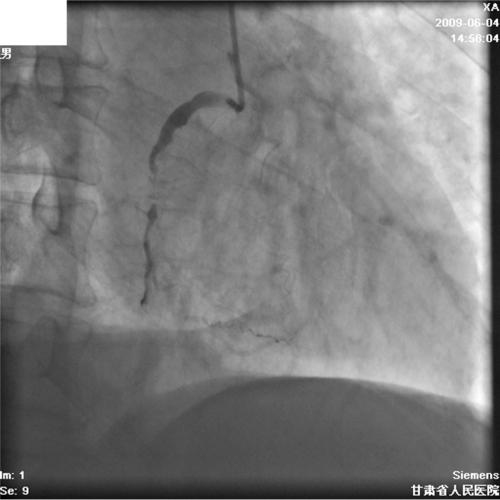

右冠状动脉经皮介入治疗期间对瓦氏窦冠状窦的广泛解剖——病例报告及文献综述

Extensive dissection to the coronary sinus of valsalva during percutaneous intervention in right coronary artery-a case report and literature review.

Severe retrograde dissection extending into the sinus of Valsalva is a rare complication during percutaneous coronary intervention (PCI), but life threatening. There is some literature about this complication, but this particular complication has not been previously reported in China. We present a case of coronary artery dissection during a PCI in which progressively extended retrogradely into the sinus of valsalva, and was successfully treated with stenting without an operation.

摘要

严重的逆行性夹层扩展至主动脉瓣窦是经皮冠状动脉介入治疗(PCI)期间罕见但危及生命的并发症。关于这一并发症有一些文献报道,但在中国此前尚未报道过这种特殊的并发症。我们报告一例PCI期间冠状动脉夹层病例,该夹层逐渐逆行扩展至主动脉瓣窦,并成功通过支架置入治疗,未进行手术。